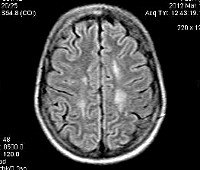

С целью диагностики вида метаболической аномалии проводится целый ряд биохимических тестов с определением уровня ферментов и накапливающихся метаболитов. Очаги демиелинизации хорошо визуализируются при помощи МРТ, могут быть обнаружены и на КТ головного мозга. Обычно демиелинизация видна на МРТ головного мозга еще до клинической манифестации лейкодистрофии. Благодаря развитию генетики, лейкодистрофия имеет разработанную ДНК-диагностику, а отдельные ее формы (метахроматическая, адренолейкодистрофия, глобоидно-клеточная) - возможность пренатального диагностирования.